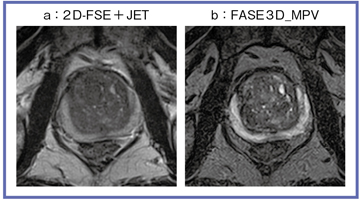

●Titan 3TでのFASE3D_MPVによる前立腺がん症例画像

Titan 3TのFASE3D_MPVでは,in-planeの解像度は2Dとほぼ同等で,非常に薄いスライスの画像が撮像できる。図1は,2D-FSE+JETで撮像した3mmスライスの画像との比較だが,FASE3D_MPVでは0.9mmでの撮像が可能となっている。3D-TSEでは,前立腺辺縁域の信号が高くなるため,腫瘍が明瞭に描出される。また,薄いスライスとコントラストの向上によって,移行域の結節性過形成の腺成分を反映するT2強調高信号も観察できる。今後の3Dシーケンスの調整によって,さらなる画質の向上が期待される(図2)。